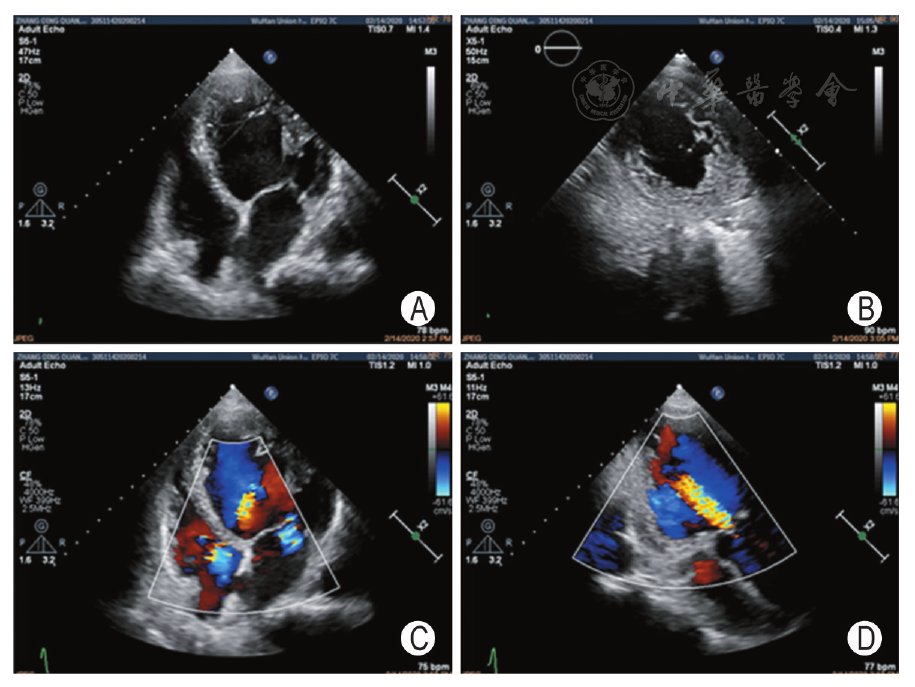

超声心动图

超声心动图图片

心脏超声心动图

超声心动图与心脏彩超

成人超声心动图

超声心动图切面

二维超声心动图

经胸超声心动图